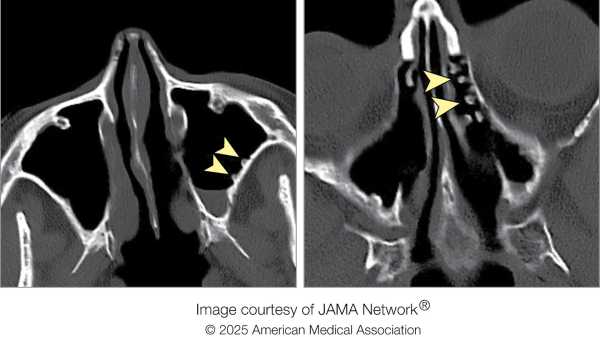

У лікарні рентгенівський знімок верхньої частини хребта чоловіка не виявив жодних відхилень. Однак посилення болю в хребті та скутість шиї спонукали одного з лікарів призначити комп'ютерну томографію (КТ) тієї ж ділянки. На КТ лікарі помітили «клиноподібний, гіперщільний об'єкт», – написали вони у звіті про випадок. Об'єкт проник у задню частину горла чоловіка та увійшов у його спинномозковий канал. Він застряг там, пробивши великий потиличний отвір – великий отвір біля основи черепа, через який проходить спинний мозок.

Діагноз: Лікарі негайно провели чоловікові операцію з видалення прониклого предмета. Вони ввели загальний наркоз, і хірург використав ретрактори — інструменти, що утримують рани відкритими, — щоб оголити предмет, який виявився зламаним кінчиком риб’ячого дзьоба.

Лікування: Гострий фрагмент дзьоба так міцно застряг у черепі чоловіка, що хірургу довелося зробити додатковий розріз над верхнім хребцем чоловіка, щоб видалити його, витягнувши вздовж шляху введення. Його довжина становила близько 3,5 сантиметрів (1,4 дюйма).

Згідно зі звітом, випадок цього чоловіка є першим зареєстрованим випадком травми великого потиличного отвору, а також першою травмою, спричиненою рибодзьобом.